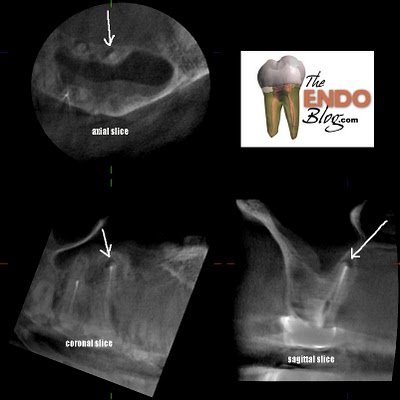

This slice through the MB root shows that there is a missed MB#2 canal.

A slice through the palatal root shows a periapical lesion on the palate not visible in the original, pre-op radiograph. This now changes our treatment recommendation. An apicoectomy will resolve the MB issues, but fail to resolve the palatal lesion. This could cause continued problems and lead to the assumption of a failed endodontic surgery, when the palatal root could be the problem.